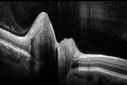

Optic Nerve (Disc) Drusen - Spectral Domain Optical Coherence Tomography Line Scan824 views34 Year Old woman no headaches normal vision